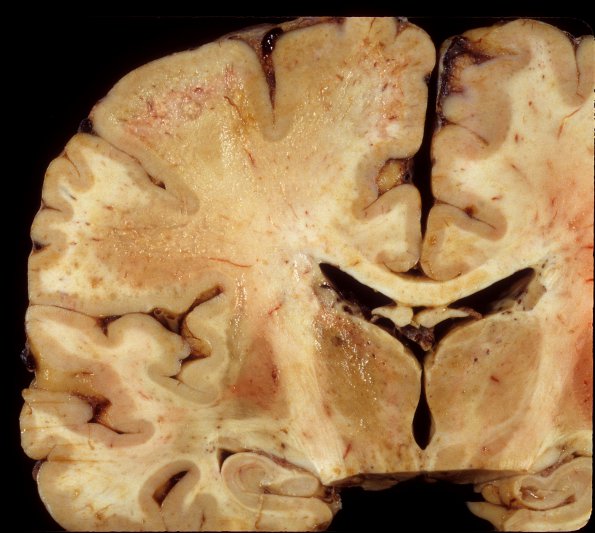

PML - Gross Pathology

4A4 PML (Case 4) 6

Higher magnification of the area shown in image #4A3.